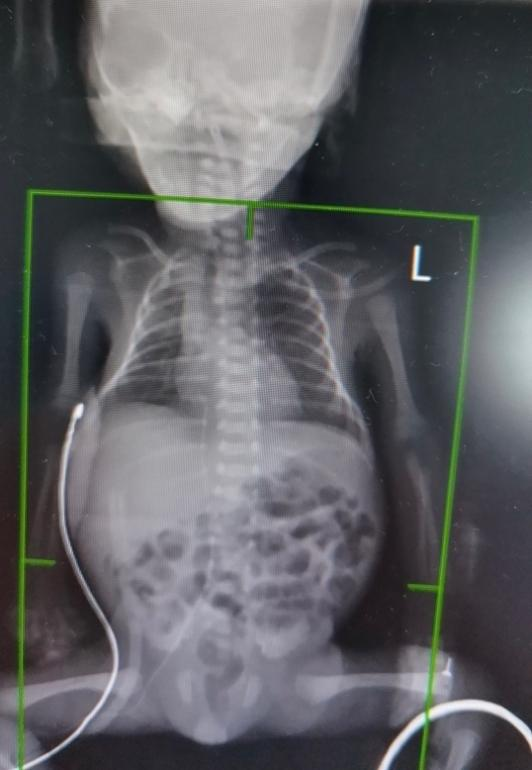

图A示患儿术后,患儿与成人手掌般大小

图B示患儿术后第5天胸腹部平片,肠气分布比好转